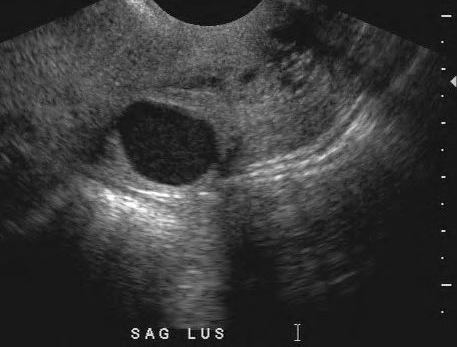

Nabothian cyst